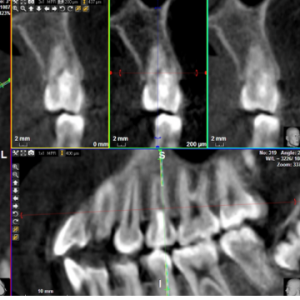

IntroducciónLos caninos mandibulares transmigrados (migrados a través de la línea media) constituyen un desafío de tratamiento. La transmigración avanzada puede tratarse con éxito mediante...

El uso de plantillas quirúrgicas está ahora muy extendido en el campo de los implantes, permitiendo la ejecución de tratamientos de rehabilitación incluso complejos de una forma más sencilla y...